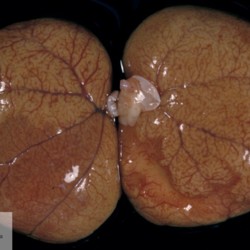

Etiquetes: N-736/97 1 total Feline Specie: Feline Organ: Kidney Lesion: Infarction Lesion modifier: Infarction - Subacute Disease: - Files/Expedient: N-736/97 Not viewed Títol Select...Avian (Exotic) (110)Avian (Poultry) (76)Bovine (317)Canine (935)Caprine (47)Equine (257)Feline (326)Ferret (19)General (127)Marine mammal (22)Non-human primate (20)Ovine (328)Porcine (379)Rabbit (61)Reptile (38)Rodent (28)Wildlife (91) Format Select...- (60)Abomasum (37)Adrenal gland (10)Blood (7)Blood vessel (50)Body as a whole (19)Bone (57)Bone marrow (21)Brain (93)Cloaca (1)Diaphragm (2)Ear (5)Esophagus (39)Eye (16)Fetus (12)Gallbladder (23)Gizzard (2)Heart (265)Intestine (356)Joint (32)Kidney (443)Larynx (5)Liver (326)Lung (264)Lymph node (91)Mammary gland (10)Mediastinum (1)Muscle (22)Nasal cavity (22)Nerve (7)Omasum (5)Oral cavity (63)Ovary (14)Oviduct (8)Pancreas (7)Parathyroid (5)Penis (10)Peritoneum (65)Pharynx (9)Pituitary gland (6)Placenta (7)Prostate (8)Proventriculus (3)Reticulum (1)Rumen (28)Sinus (7)Skin (181)Spinal cord (15)Spleen (105)Stomach (125)Teeth (1)Testicle (11)Thoracic cavity (31)Thymus (13)Thyroid gland (5)Tongue (32)Tonsils (11)Trachea (11)Urethra (5)Urinay bladder (61)Uterus (27)Vagina (1)Vulva (1)Yolk sac (1) Cobertura Select...- (152)Abomasitis (26)Abscess (27)Acidosis (1)Adenocarcinoma (20)Adenoma (9)Aerosacculitis (6)Agenesis (1)Agnathia (1)Alopecia (7)Amyloidosis (12)Aneurysm (6)Angiectasis (1)Anthracosis (1)Arteritis (11)Arthritis (15)Arthrogryposis (6)Artifact (4)Ascites (13)Atelectasis (8)Atherosclerosis (5)Atresia (1)Atrial septal defect (2)Atrophy (10)Autolysis (7)Bronchitis (6)Bronchopneumonia (26)Cachexia (2)Carcinoma (103)Cardiomyopathy (19)Cellulitis (2)Chemodectoma (4)Cholangiohepatitis (4)Cholangitis (19)Cholecystitis (4)Cholestasis (5)Chondrodysplasia (2)Chondrosarcoma (2)Chronic passive congestion (13)Chylothorax (2)Cirrhosis (6)Coelomitis (3)Coenurus cerebralis (4)Colitis (40)Congestion (17)Conjunctivitis (5)Coronitis (3)Cryptorchidism (3)Cyst (25)Cystitis (24)Dermatitis (69)Diaphragmatic hernia (4)Dilation (28)Discospondylitis (1)Disseminated intravascular coagulation (7)Dyschondroplasia (1)Dysplasia (29)Ectopia cordis (1)Ectopic ureter (1)Edema (55)Emphysema (5)Encephalitis (5)Endocardiosis (14)Endocarditis (26)Endometritis (5)Enteritis (118)Enterolith (6)Epulis (3)Esophagitis (14)Fasciitis (1)Fibrosis (7)Fibrous osteodystrophy (8)Fistula (1)Folliculitis (3)Fracture (2)Gastritis (34)Gingivitis (5)Glioma (8)Glomerulonephritis (21)Glossitis (25)Glycogenosis (1)Gout (8)Granuloma (2)Granulosa cell tumor (4)Hemangioma (9)Hemangiosarcoma (46)Hematoma (8)Hemoglobinuria (2)Hemopericardium (12)Hemoperitoneum (2)Hemorrhage (100)Hemosiderosis (7)Hemothorax (2)Hepatitis (78)Hernia (11)Histiocytosis (3)Hydatid cyst (11)Hydrocephalus (9)Hydrometra (1)Hydronephrosis (22)Hydropericardium (6)Hydrothorax (3)Hydroureter (5)Hyperkeratosis (8)Hyperostosis (4)Hyperplasia (37)Hypertrophy (9)Hypopigmentation (1)Hypoplasia (7)Hypopyon (1)Impaction (6)Infarction (63)Insulinoma (6)Intussusception (5)Jaundice (17)Laminitis (2)Laryngitis (2)Leiomyoma (5)Leukemia (13)Lipidosis (36)Lipoma (7)Lymphadenitis (45)Lymphadenopathy (7)Lymphangiectasia (6)Lymphangitis (5)Lymphoma (221)Malacia (11)Malignant melanoma (15)Mast cell tumor (11)Mastitis (8)Megaesophagus (2)Melanosis (3)Melena (4)Meningioma (6)Meningitis (6)Meningocele (2)Meningoencephalitis (5)Mesothelioma (5)Methemoglobinemia (2)Mineralization (10)Mucocele (5)Mucometra (1)Multilobular bone tumor (1)Mummification (3)Myelofibrosis (1)Myocarditis (4)Myositis (5)Necrosis (81)Nephritis (113)Nephroblastoma (6)Nephrosclerosis (1)Nephrosis (14)Neuritis (1)Obstruction (13)Omasitis (4)Omphalitis (1)Omphalophlebitis (7)Orchitis (4)Osteoarthrosis (5)Osteomyelitis (9)Otitis (2)Palatoschisis (3)Pancreatitis (3)Panniculitis (3)Papilloma (7)Parakeratosis (14)Patent ductus arteriosus (6)Peliosis hepatis (1)Perforation (17)Pericarditis (35)Peritonitis (39)Persistent right aortic arch (1)Pharyngitis (2)Pheochromocytoma (2)Phlebitis (2)Placentitis (6)Pleuritis (21)Pleuropneumonia (24)Pneumonia (109)Pneumothorax (3)Polycystosis (14)Polyp (5)Polyserositis (6)Posthitis (1)Proctitis (4)Prolapse (3)Prostatitis (3)Proventriculitis (1)Pyelonephritis (24)Pyometra (6)Pyothorax (4)Rhinitis (11)Rumenitis (6)Rupture (24)Salpingitis (3)Sarcoma (57)Sclerosis (1)Scoliosis (2)Seminoma (2)Sequestrum (2)Serous atrophy (14)Sinusitis (7)Splenitis (14)Splenomegaly (9)Spondylitis (6)Spondylosis (1)Stenosis (9)Stomatitis (32)Tenosynovitis (2)Teratoma (3)Thricobezoar (2)Thrombosis (16)Tonsilitis (4)Torsion (13)Tracheitis (4)Tympany (7)Typhlitis (8)Typhlocolitis (4)Ulcer (43)Urethritis (1)Urolithiasis (36)Uroperitoneum (1)Uveitis (1)Vasculitis (15)Ventricular septal defect (3)Volvulus (11) Matèria Select... - (14)- (1653)- (152)Abomasitis - Catarrhal (2)Abomasitis - Catarrhal-hemorrhagic (1)Abomasitis - Chronic (1)Abomasitis - Fibrinous-necrotizing (2)Abomasitis - Hyperplasic (5)Abomasitis - Hyperplasic - Chronic (1)Abomasitis - Necrotic (1)Abomasitis - Necrotizing (2)Abomasitis - Ulcerative (5)Adenocarcinoma (9)Aerosacculitis - Granulomatous (1)Amyloidosis - Chronic (1)Arteritis - Necrotic (2)Arteritis - Necrotizing (1)Arthritis - Chronic (4)Arthritis - Fibrinous-purulent (3)Arthritis - Serous (4)Arthritis - Subacute (1)Ascites - Serous (1)Atrophy - Serous (1)Bronchitis - Catarrhal (3)Bronchitis - Suppurative (1)Bronchopneumonia - Catarrhal-purulent (17)Bronchopneumonia - Fibrinous (1)Bronchopneumonia - Granulomatous (1)Bronchopneumonia - Purulent (1)Bronchopneumonia - Suppurative (5)Carcinoma - Adenocarcinoma (33)Carcinoma - Adenocarcinoma - Hepatocellular (2)Carcinoma - Adenocarcinoma - Mucinous (1)Carcinoma - Basosquamous (1)Carcinoma - Cholangiocellular (3)Carcinoma - Hepatocellular (4)Carcinoma - Metastatic (3)Carcinoma - Squamous cell carcinoma (13)Carcinoma - Transitional cell (2)Cardiomyopathy - Dilated (13)Cardiomyopathy - Hypertrophic (6)Cellulitis - Necrotizing (1)Cholangitis - Chronic (8)Cholangitis - Hyperplasic (3)Cholecystitis - Fibrinous-necrotizing (1)Coelomitis - Fibrinous (1)Coelomitis - Granulomatous (1)Colitis - Catarrhal (3)Colitis - Catarrhal-hemorrhagic (1)Colitis - Fibrinous (1)Colitis - Fibrinous-necrotizing (1)Colitis - Fibrinous-necrotizing (Diphtheritic) (6)Colitis - Granulomatous (2)Colitis - Hemorrhagic (4)Colitis - Hemorrhagic-necrotizing (3)Colitis - Necrotizing (2)Colitis - Ulcerative (6)Congestion - Chronic (2)Conjunctivitis - Hyperplasic (1)Conjunctivitis - Purulent (3)Coronitis - Ulcerative (1)Cystitis - Chronic (3)Cystitis - Fibrinous (1)Cystitis - Fibrinous-necrotizing (1)Cystitis - Follicular (1)Cystitis - Hemorrhagic (6)Cystitis - Hemorrhagic-ulcerative (1)Cystitis - Necrotizing (9)Cystitis - Perforated (1)Dermatitis - Granulomatous (14)Dermatitis - Hyperkeratotic (10)Dermatitis - Hyperplasic (proliferative) (1)Dermatitis - Hyperplastic (10)Dermatitis - Necrotizing (4)Dermatitis - Pustular (4)Dermatitis - Ulcerative (2)Dilation - Chronic (1)Discospondylitis - Necrotizing (1)Dysplasia - Follicular (5)Edema - Interstitial (6)Emphysema - Interstitial (1)Encephalitis - Granulomatous (1)Encephalitis - Nonsuppurative (1)Endocardiosis - Mitral (7)Endocardiosis - Mitral - Chronic (5)Endocarditis - Valvular (6)Endocarditis - Valvular - Mitral (7)Endocarditis - Valvular - Pulmonic (1)Endocarditis - Valvular - Subacute (1)Endocarditis - Valvular - Subaortic (5)Endocarditis - Valvular - Tricuspid (4)Endometritis - Purulent (3)Endometritis - Purulent-hemorrhagic (2)Enteritis - Catarrhal (23)Enteritis - Catarrhal - Acute (1)Enteritis - Catarrhal-hemorrhagic (5)Enteritis - Catarrhal-hemorrhagic - Acute (2)Enteritis - Fibrinous (16)Enteritis - Fibrinous - Acute (3)Enteritis - Fibrinous-necrotizing (7)Enteritis - Granulomatous (14)Enteritis - Granulomatous - Chronic (1)Enteritis - Granulomatous - Multifocal (1)Enteritis - Hemorrhagic (17)Enteritis - Hemorrhagic - Acute (1)Enteritis - Hemorrhagic-necrotizing (1)Enteritis - Hyperplasic (proliferative) (4)Enteritis - Necrotizing (4)Enteritis - Necrotizing - Acute (1)Enteritis - Necrotizing - Hemorrhagic (1)Enteritis - Necrotizing-ulcerative (2)Enteritis - Ulcerative (1)Enteritis - Ulcerative-hemorrhagic (1)Esophagitis - Erosive-ulcerative (6)Esophagitis - Necrotizing (4)Esophagitis - Ulcerative (1)Esophagitis - Ulcerative-necrotizing (1)Fasciitis - Fibrinous-purulent (1)Folliculitis - Purulent (2)Gastritis - Catarrhal (2)Gastritis - Chronic (1)Gastritis - Follicular (1)Gastritis - Hemorrhagic (2)Gastritis - Hemorrhagic-necrotizing (1)Gastritis - Hypertrophic (2)Gastritis - Inclusion bodies (1)Gastritis - Mineralization (1)Gastritis - Mycotic (1)Gastritis - Necrotizing (2)Gastritis - Ulcerative (6)Gastritis - Uremic (3)Gingivitis - Erosive (2)Gingivitis - Hyperplasic (proliferative) (1)Gingivitis - Necrotizing (1)Glomerulonephritis - Chronic (7)Glomerulonephritis - Membranoproliferative (3)Glomerulonephritis - Membranoproliferative - Chronic (1)Glomerulonephritis - Membranous (3)Glomerulonephritis - Membranous - Chronic (1)Glomerulonephritis - Proliferative (2)Glomerulonephritis - Subacute (1)Glossitis - Erosive (2)Glossitis - Granulomatous (6)Glossitis - Hyperplasic (1)Glossitis - Hyperplasic (proliferative) (2)Glossitis - Hyperplastic (1)Glossitis - Necrotizing (2)Glossitis - Necrotizing - Focal (1)Glossitis - Ulcerative (6)Glossitis - Ulcerative - Multifocal (1)Glossitis - Ulcerative - Subacute (1)Glycogenosis (1)Granuloma - Eosinophilic (1)Hemangiosarcoma - Metastatic (2)Hemorrhage - Acute (1)Hemorrhage - Subcapsular (3)Hepatitis - Abscess (9)Hepatitis - Acute (3)Hepatitis - Chronic (4)Hepatitis - Chronic interstitial (6)Hepatitis - Granulomatous (7)Hepatitis - Interstitial - Multifocal (1)Hepatitis - Interstitial - Subacute (1)Hepatitis - Necrotizing (17)Hepatitis - Necrotizing - Acute (2)Hepatitis - Necrotizing - Hemorrhagic (1)Hepatitis - Necrotizing - Subacute (1)Hepatitis - Pyogranulomatous (7)Hepatitis - Subacute (4)Hydronephrosis - Chronic (1)Hydropericardium - Chronic (1)Hyperplasia - Erythroid (1)Hyperplasia - Lymphoid (3)Hyperplasia - Myeloid (1)Hyperplasia - Nodular (8)Hypertrophy - Concentric (2)Hypertrophy - Eccentric (3)Infarction - Acute (17)Infarction - Acute - Multifocal (2)Infarction - Chronic (5)Infarction - Chronic - Multifocal (1)Infarction - Subacute (18)Infarction - Subacute - Focal (2)Laminitis - Chronic (2)Laryngitis - Necrotic (1)Laryngitis - Necrotizing (1)Leukemia - Lymphoid leukemia (2)Leukemia - Non-lymphoid leukemia (6)Lipidosis - Multifocal (1)Lipidosis - Panlobular (1)Lipidosis - Panlobular - Generalized (2)Lymphadenitis - Granulomatous (24)Lymphadenitis - Granulomatous - Chronic (3)Lymphadenitis - Hemorrhagic (1)Lymphadenitis - Necrotizing (5)Lymphadenitis - Necrotizing (caseous) (11)Lymphangitis - Granulomatous (1)Lymphangitis - Purulent (1)Lymphangitis - Ulcerative (1)Lymphoma - Alimentary lymphoma (7)Lymphoma - Cutaneous lymphoma (6)Lymphoma - Lymphosarcoma (2)Lymphoma - Mediastinal lymphoma (1)Lymphoma - Multicentric lymphoma (29)Malignant melanoma - Malignant (1)Malignant melanoma - Metastatic (1)Mast cell tumor - Metastatic (1)Mastitis - Fibrinous-purulent (2)Mastitis - Necrotic (1)Mastitis - Purulent (3)Mastitis - Suppurative (1)Meningitis - Fibrinous-purulent (2)Meningitis - Purulent (4)Meningoencephalitis - Necrotizing (3)Meningoencephalitis - Nonsuppurative (2)Mineralization - Metastatic (4)Myocarditis - Fibrous - Chronic (1)Myocarditis - Granulomatous (1)Myositis - Purulent (2)Necrosis - Acute (1)Necrosis - Cortical (5)Necrosis - Follicular (1)Necrosis - Papillary (8)Necrosis - Papillary - Acute (3)Necrosis - Subacute (3)Necrosis - Tubular (6)Nephritis - Embolic (2)Nephritis - Embolic suppurative (7)Nephritis - Granulomatous (27)Nephritis - Granulomatous - Chronic (1)Nephritis - Granulomatous - Multifocal (1)Nephritis - Interstitial (6)Nephritis - Interstitial - Acute (4)Nephritis - Interstitial - Chronic (41)Nephritis - Interstitial - Subacute (12)Nephritis - Purulent (7)Nephritis - Purulent - Acute (2)Nephritis - Purulent - Multifocal (3)Nephrosis - Cholemic (3)Nephrosis - Hemoglobinuric (10)Omasitis - Fibrinous-necrotizing (1)Omasitis - Hyperkeratotic (1)Omasitis - Necrotizing (2)Omphalophlebitis - Fibrinous-purulent (2)Omphalophlebitis - Purulent (3)Orchitis - Necrotizing (1)Osteomyelitis - Necrotizing (7)Osteomyelitis - Purulent (2)Otitis - Necrotizing (1)Otitis - Proliferative (1)Pancreatitis - Acute (1)Pancreatitis - Chronic (1)Pancreatitis - Granulomatous (1)Panniculitis - Fibrinous-purulent (1)Panniculitis - Necrotic (1)Panniculitis - Parasitic (1)Perforation - Acute (2)Pericarditis - Fibrinous (19)Pericarditis - Fibrinous - Subacute (1)Pericarditis - Fibrinous-necrotizing (1)Pericarditis - Fibrinous-purulent (3)Pericarditis - Fibrous (1)Pericarditis - Fibrous - Chronic (1)Pericarditis - Gangrenous (6)Pericarditis - Granulomatous (1)Pericarditis - Granulomatous - Chronic (2)Peritonitis - Acute (1)Peritonitis - Fibrinous (11)Peritonitis - Fibrinous - Subacute (1)Peritonitis - Fibrinous-purulent (5)Peritonitis - Fibrous (3)Peritonitis - Granulomatous (6)Peritonitis - Purulent (1)Peritonitis - Purulent-hemorrhagic (1)Peritonitis - Pyogranulomatous (3)Pharyngitis - Fibrinous-necrotizing (1)Pharyngitis - Ulcerative (1)Pheochromocytoma - Metastatic (1)Phlebitis - Purulent (1)Placentitis - Fibrinous-necrotizing (1)Placentitis - Necrotic (1)Placentitis - Necrotizing (1)Pleuritis - Chronic (1)Pleuritis - Fibrinous (3)Pleuritis - Fibrinous-purulent (2)Pleuritis - Fibrous (2)Pleuritis - Granulomatous (3)Pleuritis - Hyperplastic (2)Pleuritis - Purulent (2)Pleuritis - Pyogranulomatous (1)Pleuropneumonia - Fibrinous (13)Pleuropneumonia - Fibrinous-necrotizing (5)Pleuropneumonia - Granulomatous (2)Pleuropneumonia - Hemorrhagic-necrotizing (4)Pneumonia - Aspiration (11)Pneumonia - Bronchointerstitial (4)Pneumonia - Bronchointerstitial - Subacute (1)Pneumonia - Embolic (5)Pneumonia - Granulomatous (37)Pneumonia - Granulomatous - Multifocal (4)Pneumonia - Hemorrhagic-necrotizing (2)Pneumonia - Interstitial (7)Pneumonia - Interstitial - Acute (8)Pneumonia - Interstitial - Chronic (6)Pneumonia - Interstitial - Subacute (15)Pneumonia - Necrotizing (2)Pneumonia - Pyogranulomatous (2)Pneumonia - Verminous (5)Polyserositis - Fibrinous (6)Polyserositis - Fibrous (1)Proctitis - Fibrinous-necrotizing (1)Proctitis - Parasitic (2)Prostatitis - Purulent (1)Pyelonephritis - Acute (2)Pyelonephritis - Chronic (3)Rhinitis - Catarrhal (2)Rhinitis - Fibrinous (1)Rhinitis - Granulomatous (4)Rhinitis - Purulent (3)Rumenitis - Acute (1)Rumenitis - Erosive (1)Rumenitis - Necrotizing (1)Rupture - Acute (3)Sarcoma - Fibrosarcoma (12)Sarcoma - Hemangiosarcoma (11)Sarcoma - Histiocytic (7)Sarcoma - Metastatic (1)Sarcoma - Multilobular tumor of bone (1)Sequestrum - Chronic (2)Sinusitis - Suppurative (1)Splenitis - Granulomatous (8)Splenitis - Granulomatous - Chronic (1)Splenitis - Necrotizing (3)Splenitis - Necrotizing (caseous) (2)Spondylitis - Necrotizing (2)Stenosis - Intestinal (1)Stenosis - Valvular - Subaortic (4)Stomatitis - Erosive (12)Stomatitis - Erosive-ulcerative (3)Stomatitis - Fibrinous-necrotizing (1)Stomatitis - Fibrinous-necrotizing (Diphtheritic) (1)Stomatitis - Granulomatous (1)Stomatitis - Hyperplasic (1)Stomatitis - Hyperplasic (proliferative) (1)Stomatitis - Necrotizing (2)Stomatitis - Ulcerative (5)Stomatitis - Ulcerative - Multifocal (1)Stomatitis - Ulcerative-necrotizing (1)Tonsilitis - Necrotizing (4)Torsion - Acute passive hyperemia (5)Tracheitis - Catarrhal (3)Tracheitis - Fibrinous (1)Tracheitis - Granulomatous (1)Typhlitis - Catarrhal (1)Typhlitis - Fibrinous-necrotizing (2)Typhlitis - Hemorrhagic (2)Typhlitis - Ulcerative-hemorrhagic (1)Typhlocolitis - Fibrinous-necrotizing (2)Typhlocolitis - Proliferative (1)Ulcer - Chronic (6)Ulcer - Multifocal (2)Ulcer - Mycotic (1)Ulcer - Perforated (6)Urethritis - Hemorrhagic (1)Urolithiasis - Chronic (2)Uveitis - Granulomatous (1)Vasculitis - Granulomatous (1)Vasculitis - Necrotizing (1) Editor Select...- (1970)Acidosis (2)Actinobacillosis (Pleuropneumonia) (11)Aelurostrongylosis (2)African horse sickness (13)African swine fever (14)Alopecia X (1)Anaplasmosis (4)Anthrax (2)Aortic thromboembolism (feline) (7)Ascariasis (15)Aspergillosis (18)Atopic dermatitis (1)Atrophic rhinitis (3)Babesiosis (6)Blackhead (1)Bluetongue (11)Border disease (2)Bovine viral diarrhea (21)Brucellosis (2)Candidiasis (5)Canine distemper (14)Caprine arthritis-encephalitis (2)Capture myopathy (1)Cardiac insufficiency (17)Caseous lymphadenitis (7)Chlamydiosis (2)Classical swine fever (19)Clostridiosis (19)Coccidiosis (9)Coenurosis (4)Colibacillosis (21)Contagious ecthyma (7)Copper toxicosis (11)Cowdriosis (Heartwater) (3)Cryptococcosis (3)Cryptosporidiosis (2)Cysticercosis (23)Demodicosis (1)Diabetes (1)Dicrocoeliosis (5)Dictyocaulosis (4)Dirofilariasis (7)Discoid lupus erythematosus (3)Echinococcosis (17)Edema disease (7)Egg drop syndrome (1)Encephalitozoonosis (5)Enterotoxemia (1)Enzootic bovine leukosis (46)Epitheliogenesis imperfecta (3)Equine rhinopneumonitis (2)Equine verminous arteritis (strongylosis) (7)Erysipelas (5)Exudative epidermitis (7)Fasciolasis (11)Feline eosinophilic dermatoses (1)Feline hepatic lipidosis (8)Feline histiocytosis (4)Feline infectious peritonitis (38)Feline leukemia (4)Feline lower urinary tract disease (3)Feline panleukopenia (16)Feline viral rhinotracheitis (1)Flea allergy dermatitis (1)Foot and mouth disease (2)Gasterophilosis (4)Glasser's disease (15)Gousiekte (4)Gout (6)Haemonchosis (9)Hemolytic anemia (4)Hemorrhagic diathesis (1)Hepatic insufficiency (11)Hepatosis dietetica (7)Herpesvirosis (6)Hyperadrenocorticism (7)Hyperparathyroidism (10)Hypertrophic osteopathy (6)Hypervitaminosis D (1)Hypodermosis (1)Inclusion body hepatitis (4)Infectious bovine rhinotracheitis (5)Infectious bronchitis (5)Infectious canine hepatitis (13)Influenza (4)Juvenile nephropathy (8)Lamb dysentery (4)Leishmaniasis (28)Leptospirosis (1)Leukosis (5)Listeriosis (4)Lumpy skin disease (3)Maedi-visna (4)Malignant catarrhal fever (12)Mange (6)Mannheimiosis (5)Marek's disease (7)Metabolic bone disease (2)Mucoid enteropathy (5)Mulberry heart disease (5)Myasis (1)Mycobacteriosis (22)Mycosis fungoides (6)Myxomatosis (3)Necrobacillosis (5)Neonatal isoerythrolysis (6)Nocardiosis (4)Oestrosis (2)Onchocerciasis (1)Osteochondrosis (1)Ostertagiosis (6)Ovine pulmonary adenocarcinoma (5)Oxyuriasis (1)Pacheco's disease (4)Papillomatosis (6)Paratuberculosis (18)Parvovirosis (17)Pasteurellosis (11)Pemphigus foliaceus (1)Periodontal disease (1)Polioencephalomalacia of ruminants (4)Polyarteritis nodosa (3)Polycystic kidney disease (13)Porcine circovirosis (11)Porcine dermatitis and nephropathy syndrome (9)Porcine proliferative enteropathy (4)Porcine reproductive and respiratory syndrome (6)Porcine stress syndrome (1)Pox (13)Pregnancy toxemia (3)Proventricular dilatation disease (2)Pseudotuberculosis (yersiniosis) (2)Psittacine beak and feather disease (PBFD) (5)Pyoderma (4)Q fever (4)Rabbit hemorrhagic disease (2)Renal insufficiency (12)Reticuloendotheliosis (2)Rhodococcosis (1)Rickets (1)Rinderpest (2)Salmonellosis (34)Sarcosporidiosis (2)Schmallenberg (7)Septicemia (23)Spirocercosis (11)Streptococcosis (5)Strongylosis (1)Swine dysentery (5)Systemic coronavirosis (5)Tetralogy of Fallot (5)Theileriosis (13)Thromboembolism (5)Toxoplasmosis (11)Transmissible viral proventriculitis (1)Traumatic reticuloperitonitis (3)Traumatism (16)Tuberculosis (58)Ulcerative lymphangitis (1)Uremic syndrome (20)Viral arthritis (6)White muscle disease (9)Wobbler syndrome (2)Xanthomatosis (1)Zygomycosis (4) Idioma Select...- (1180)Bacterial (501)Degeneration (106)Fungal (46)Hemodynamic (112)Idiopathic (22)Inflammation (58)Malformation (88)Neoplasia (343)Nutritional (41)Parasitic (243)Physical/Chemical (93)Toxic (44)Viral (304) Ítem destacat Bovine Spleen is larger than 50 cm. University of Pretoria, South Africa